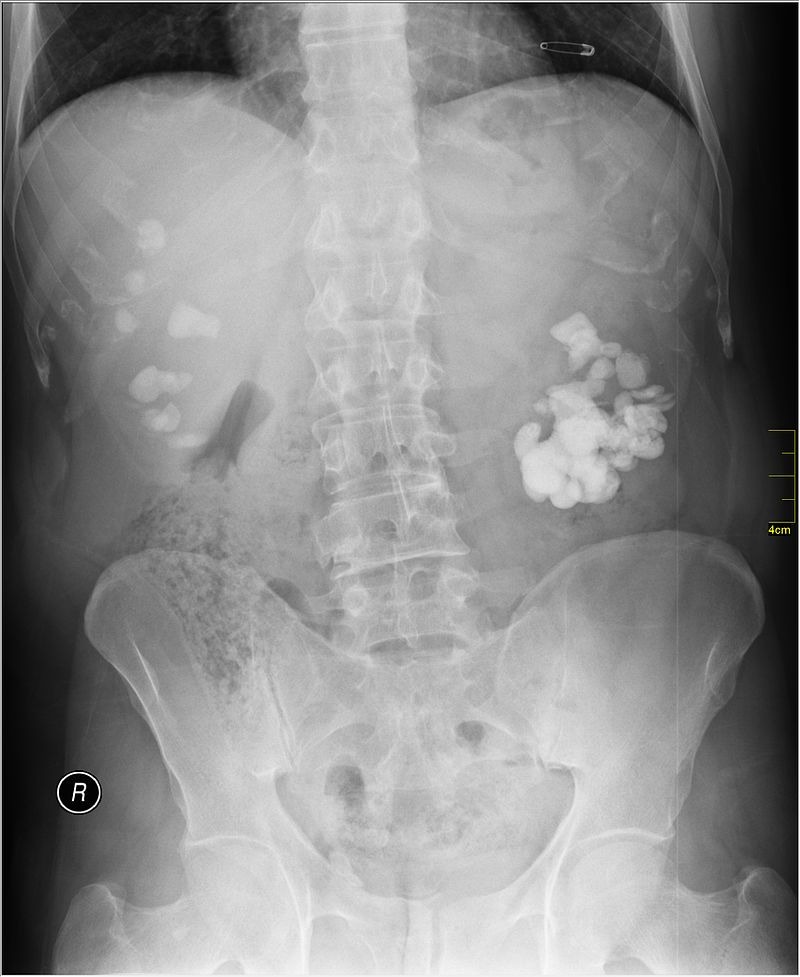

Căn cứ vào kết luận sơ bộ khi kiểm tra lâm sàng, các bác sĩ sẽ yêu cầu bệnh nhân thực hiện một số phương pháp chẩn đoán khác. Các phương pháp chẩn đoán hình ảnh như chụp X-quang sẽ được áp dụng để kiểm tra sự có mặt của sỏi cản quang. Hay kỹ thuật siêu âm cũng được dùng để kiểm tra hình ảnh chi tiết về loại sỏi, kích thước sỏi thận và vị trí của chúng trong thận và bàng quang. Ngoài ra, xét nghiệm máu và xét nghiệm nước tiểu sẽ được thực hiện để xác định các chỉ số cơ bản và đánh giá chức năng thận.